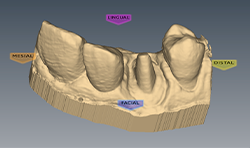

The implant in the tooth #12 area on the 50-year-old female patient is ready for restoration. In this instance, a stock abutment was selected and prepared extraorally. The abutment was placed to 25 ncm torque.

The PlanmecaFit with the Planmeca Emerald™ scanner (Figs. 7-8) was used to take a set of digital impressions, and the restoration was milled in the PlanMill® 40 S using an Ivoclar Vivadent IPS e.max block shade A1.

The milled restoration (Fig. 9) was crystallized and glazed in an Ivoclar Vivadent Programat CS2 oven.

The restoration was seated (Figs. 10-11), contacts and occlusion checked, and luted into place with Ivoclar Vivadent SpeedCem composite luting cement.